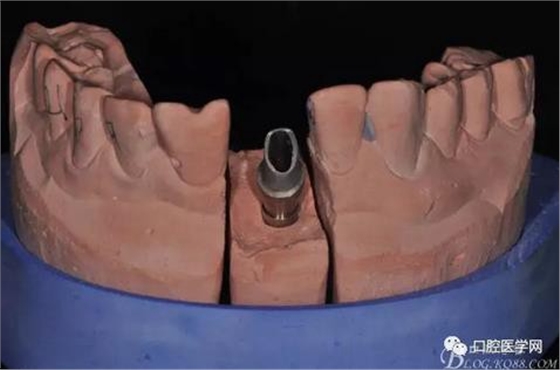

圖16 修復(fù)基臺(tái)模型頜面照